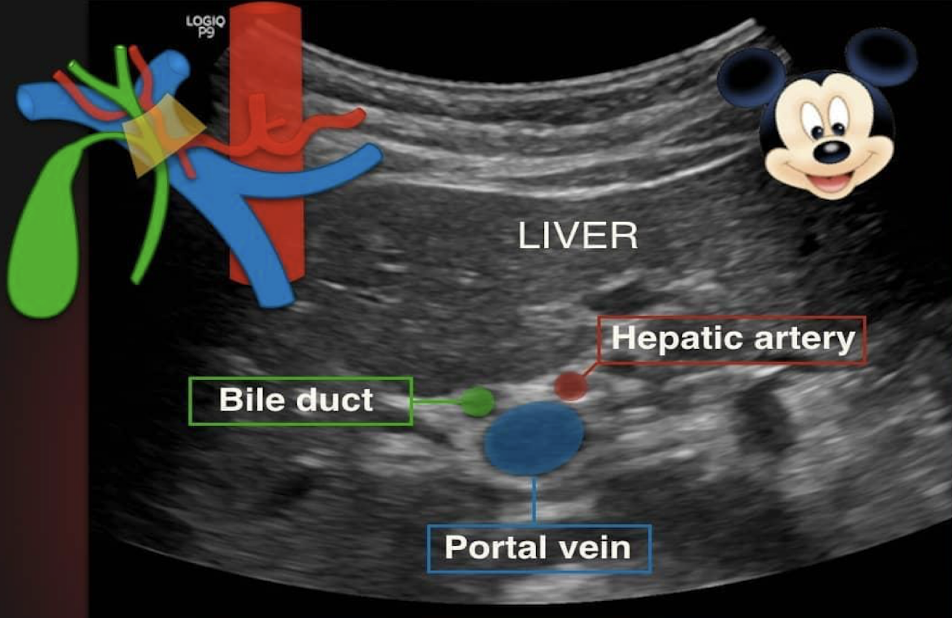

portal triad consists of what?

portal vein (head)

duct (right ear)

hepatic artery (left ear)